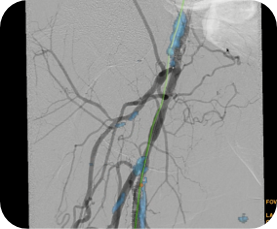

Guider